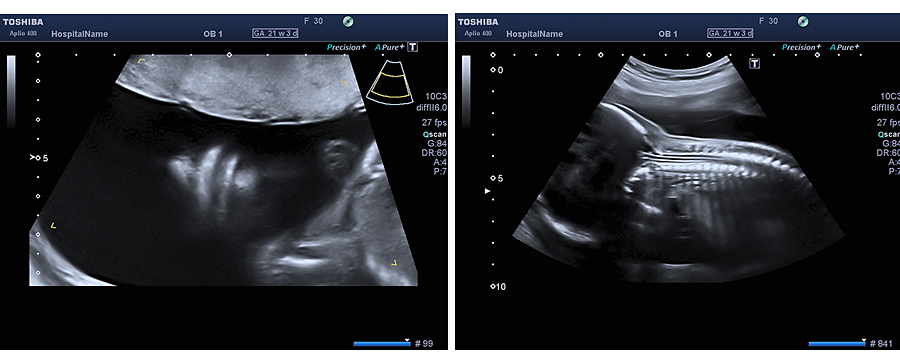

In der Zeit von der vollendeten 19. bis zur vollendeten 22. Schwangerschaftswoche kann das ungeborene Kind sehr viel detaillierter und umfangreicher als in dem von den Mutterschaftsrichtlinien vorgesehenen Ultraschall untersucht werden.

Bei dieser Ultraschalluntersuchung werden alle einsehbaren Organe des Kindes detailliert beurteilt sowohl in Hinblick auf Ihre korrekte Ausbildung als auch auf ihre korrekte zeitliche Entwicklung. Eine besonders wichtige Stellung nimmt hierbei die Beurteilung der Entwicklung und Funktion des kindlichen Herzens (Echokardiographie) ein. Des weiteren wird die Fruchtwassermenge, sowie die Lage und das Aussehen des kindlichen Mutterkuchens beurteilt.

Bei sachgerecht durchgeführter Untersuchung können also im Rahmen dieser „Feindiagnostik“ Fehlentwicklungen und Fehlbildungen ungeborener Kinder aufgedeckt werden und ggf. schon frühzeitig im Mutterleib therapiert werden (z.B. bei Herzrhytmusstörungen, einigen Infektionen etc.), Entscheidungen über eine eventuell notwendige nachgeburtliche Therapie (Operation eines Herzfehlers oder einer angeborenen Lippen-Kiefer-Gaumenspalte) getroffen werden, der Geburtsmodus (Kaiserschnitt oder Spontangeburt) und auch die Entbindungsklinik (ggf. Klinik mit angegliederter Kinderklinik) festgelegt werden.

Auch können bei dieser Untersuchung ähnlich wie beim First-Trimester-Screening so genannte Marker auffallen, die an sich keine Fehlbildung darstellen, und keinerlei Einfluss auf die Entwicklung der betroffenen Organe und damit des Kindes zeigen, welche jedoch das Risiko für das Vorhanden einer Chromosomenstörung erhöhen. Zu diesen Markern gehören im zweiten Drittel der Schwangerschaft zum Beispiel eine Verkürzung der Oberschenkel und Oberarme, eine Verbreiterung der Nierenbecken, Auffälligkeiten im Bereich des Magen-Darm-Kanals etc.

Diese detaillierte Ultraschalluntersuchung kann natürlich auch zu jedem späteren Zeitpunkt der Schwangerschaft durchgeführt werden, ist jedoch in der 19. - 22. Schwangerschaftswoche am aussagekräftigsten.